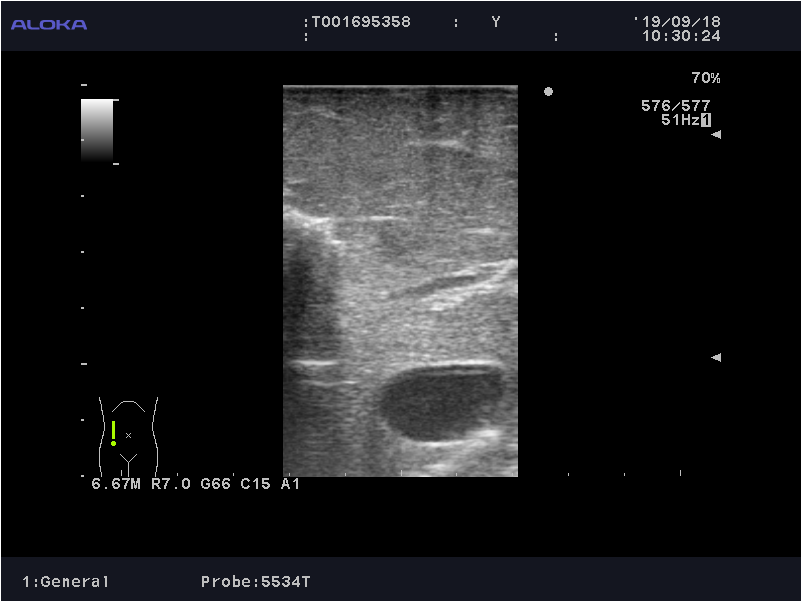

2019-09-05 北肿腹部超声示:肝S4肝中静脉旁可见低回声结节,大小约12x9mm,边界欠清,肝门处可见多发小淋巴结,性质待定。

(SonoVue),动脉期可见肝S4肝中静脉旁病灶轻度环状强化,实质期廓清呈低增强,病灶大小约10x9mm,考虑转移灶治疗后改变。第2次经静脉团注法注射SonoVue,肝S7近膈病灶动脉期由周边向中心逐渐强化,实质期呈高增化,病灶大小约15x9mm,考虑血管瘤。

4.术中超声检查肝脏;

探查腹腔,未见腹水。肝脏呈化疗后蓝肝改变。术中超声检查确认转移瘤位于左肝S4。阻断第一肝门,以PMOD沿预定切除线分离肝实质,完整切除肿瘤,解剖肝十二指肠韧带,清除所属淋巴脂肪组织,显露肝动脉、门静脉及胆总管使之骨骼化。

图6.术中超声